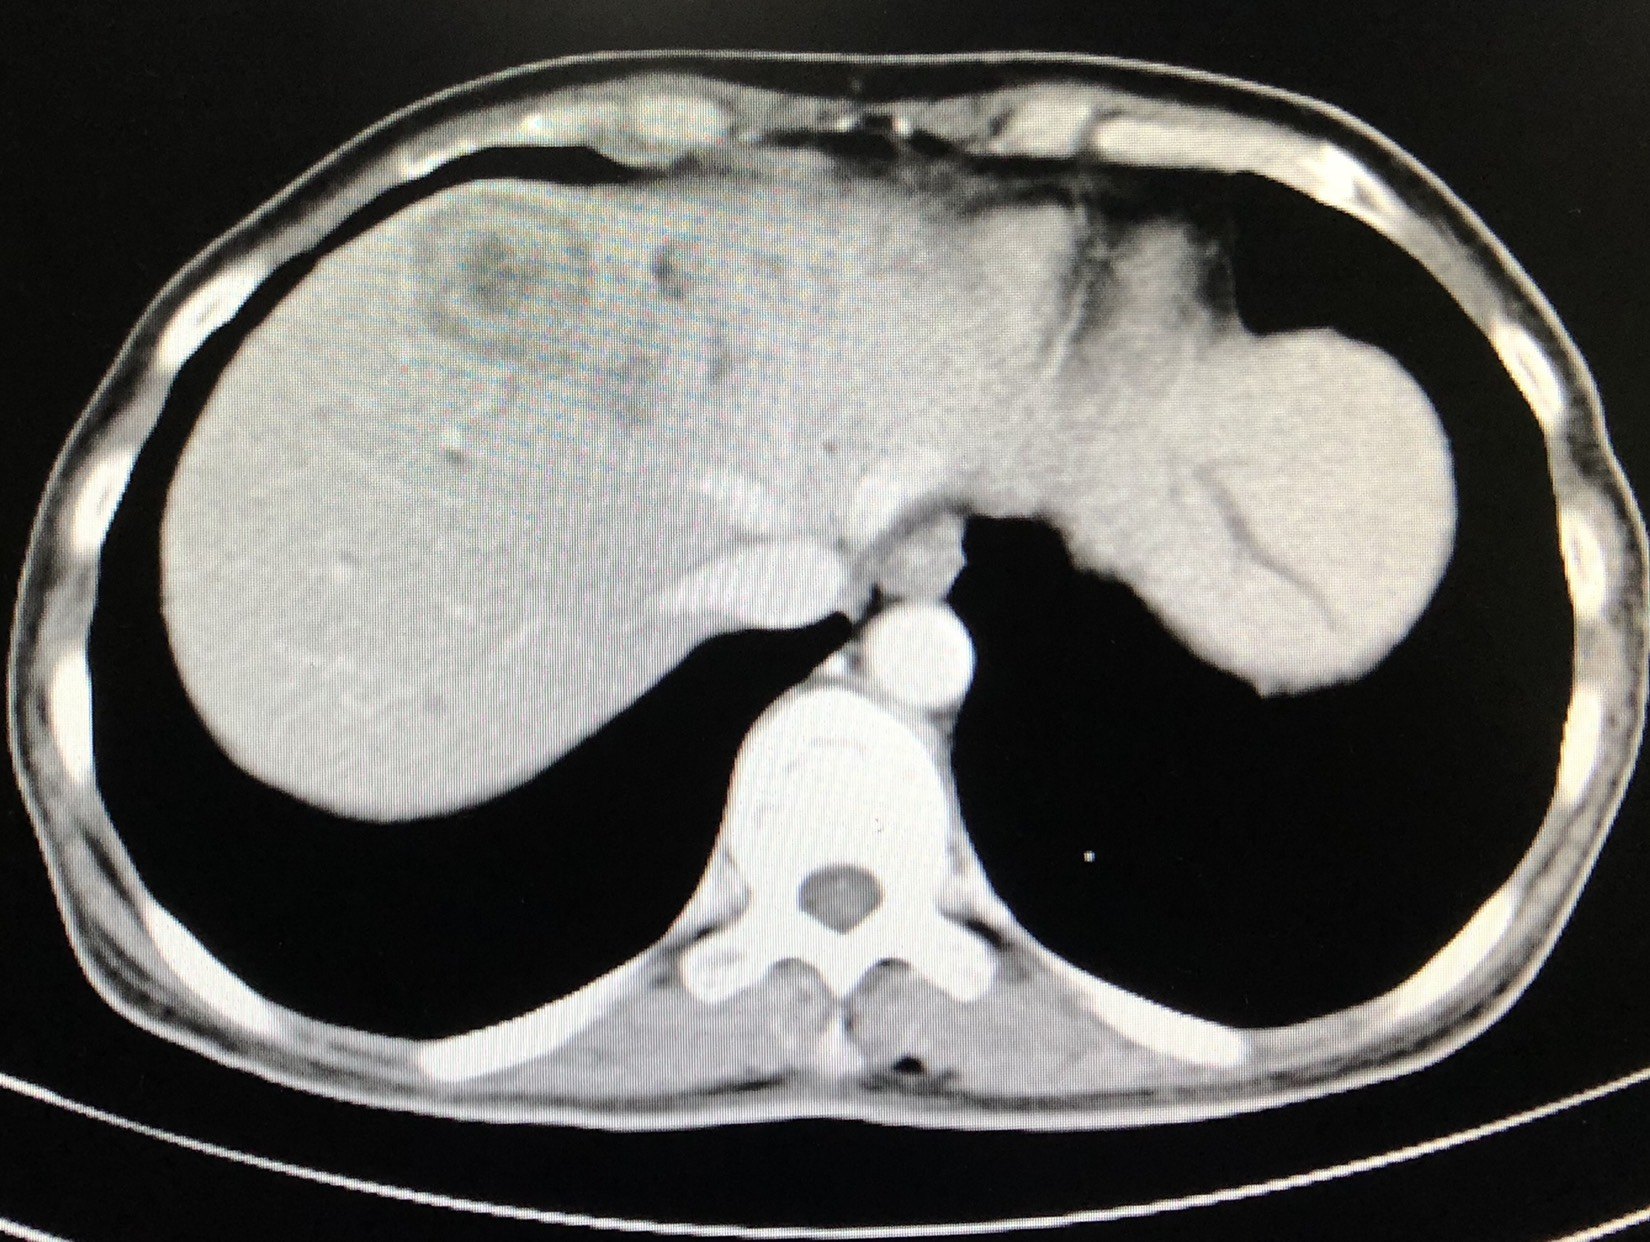

术前ct提示肝右叶转移瘤